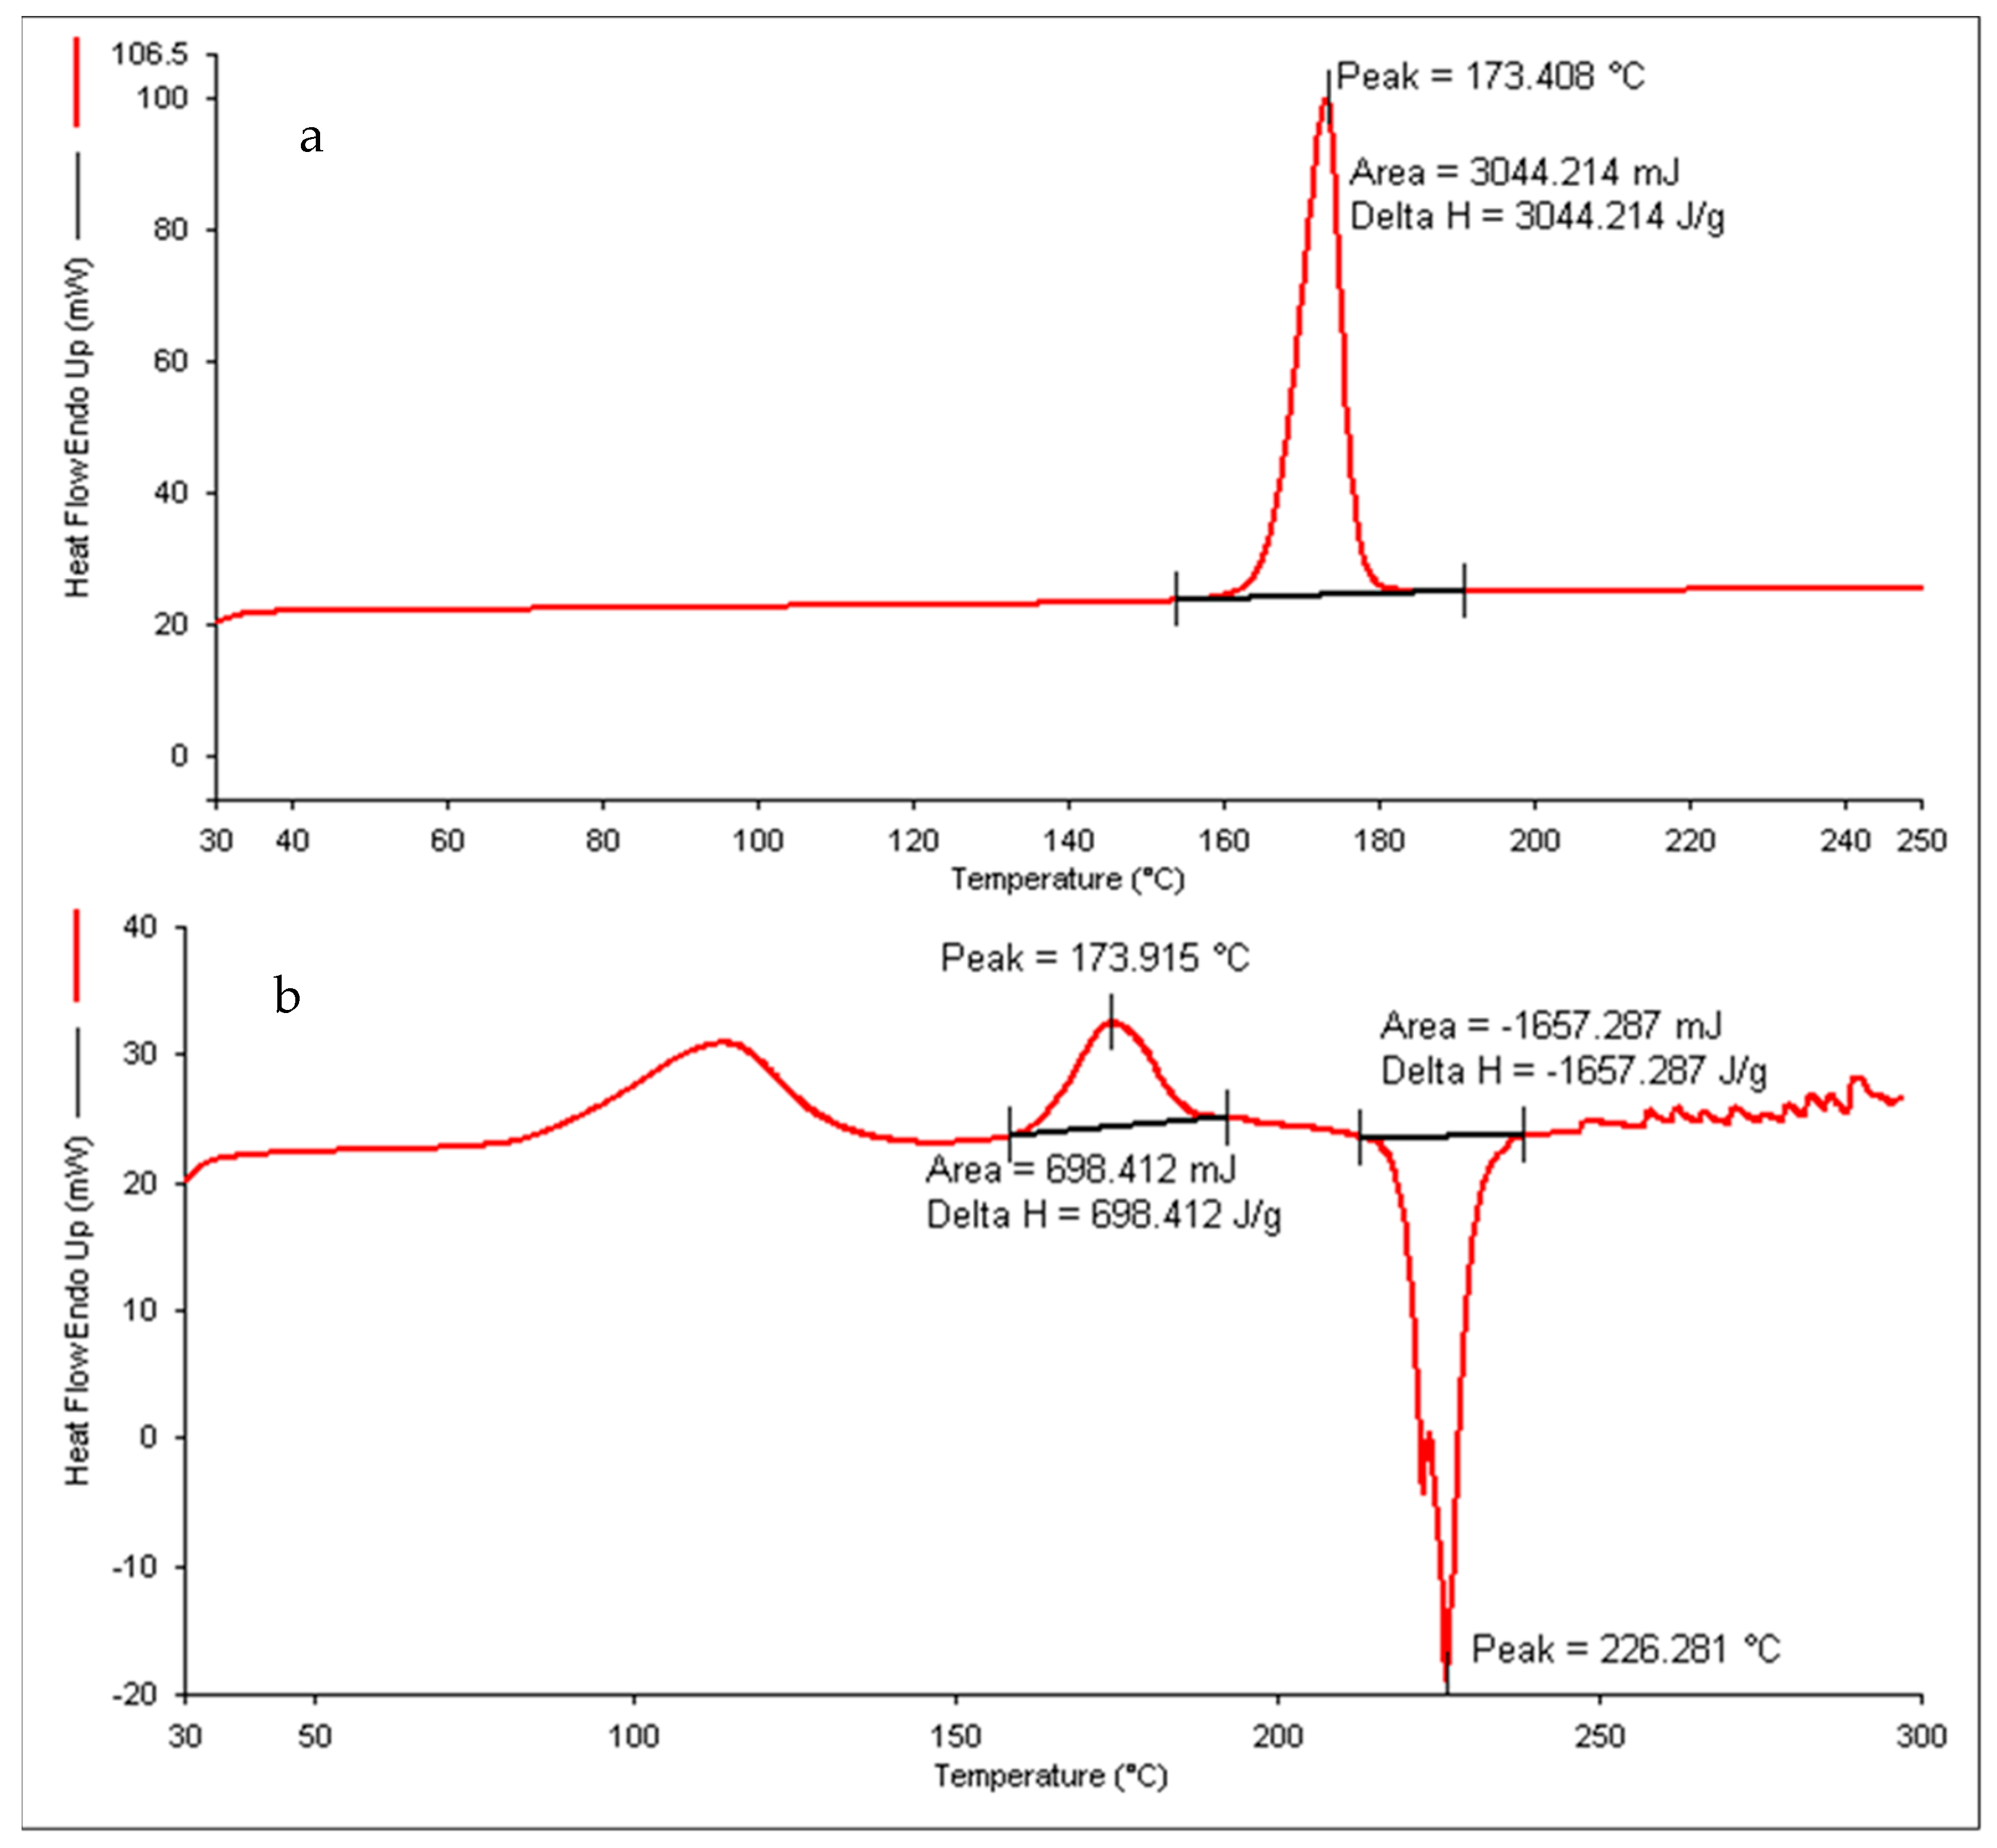

2.7.5. Differential Scanning Colorimetry

3.6.4. Differential Scanning Calorimeter